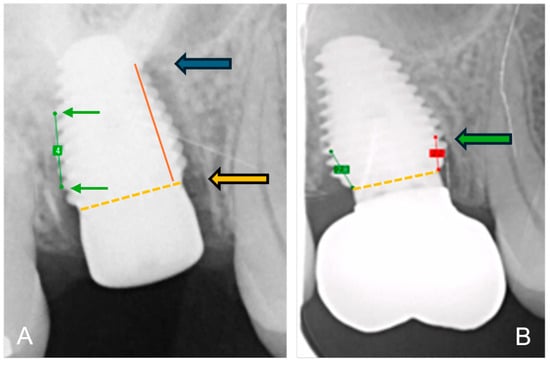

The bone-to-implant contact levels were digitally measured on digital peri-apical radiographs (Software Exquise Classic v.2024, Vertimart, Kwadijk, The Netherlands). According to the workflow applied in the clinic, periapical radiographs were taken after surgery (baseline), after loading, and at the last available recall appointment. In case the implant threads were unclear, related to misalignment of the Röntgen beam, a new radiograph was taken. The distance from the implant-abutment interface to the most coronal bone-to-implant contact was measured both mesially and distally at each of these time points. Measurement errors, due to magnification or angulation of the radiograph, were corrected by calibration with the known distance of 5 implant threads. Three master students, not involved in the actual treatment, measured the radiographs. They were calibrated, and inter-examiner and intra-examiner reliability was assessed by repeating the measurements of 24 implant cases within a 2-week interval. Bone loss at the time of loading and final recall was calculated by subtraction in relation to baseline. Figure 2 demonstrates the method of radiographical assessment of bone levels over time.

Figure 2.

Method of radiographical assessment of an immediately placed MAX implant in a molar. Extraction socket; (A) after surgery: green line is the calibrated measurement of 5 implant pitch threads corresponding to 4 mm in reality; the orange dotted line indicates the implant-abutment interface and the orange arrow indicates the reference point; the red line the distance from bone level to reference point and the blue arrow indicates bone level at baseline immediately after surgery; (B) at final recall: the green arrow indicates the bone level at final recall; the red line the distance from bone level to reference point.